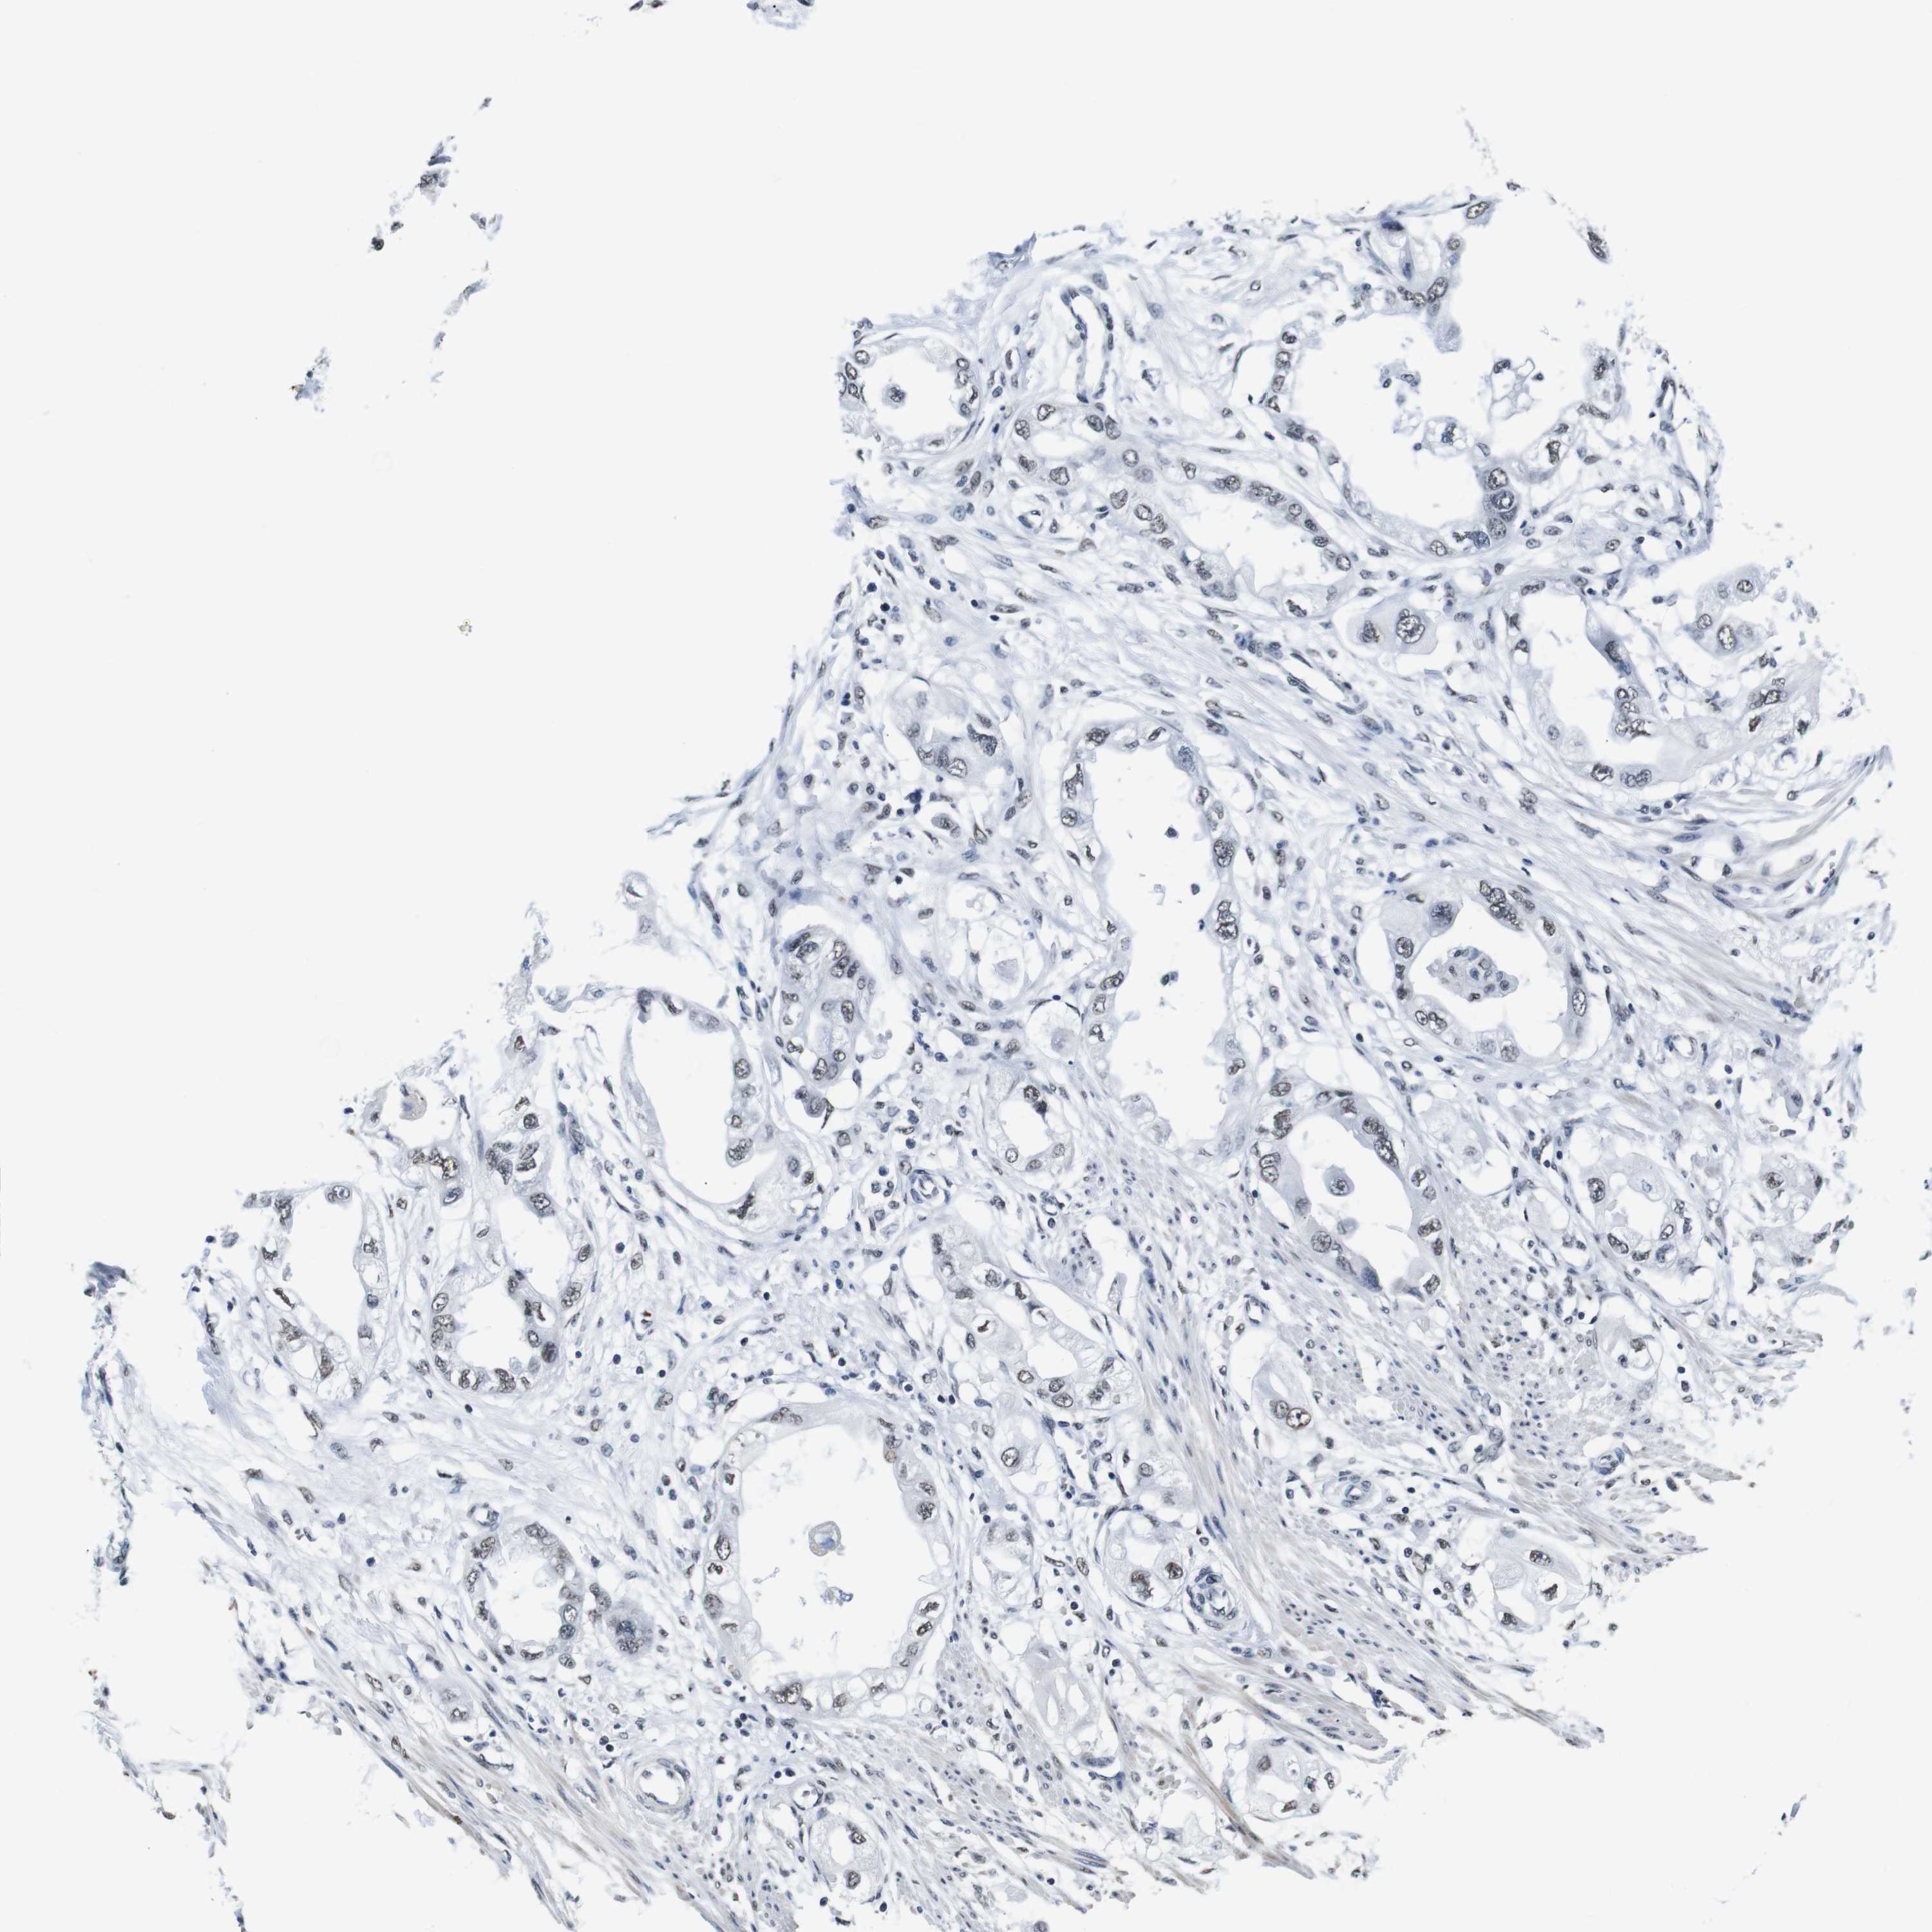

ENDOMETRIAL CANCER - Protein expressioni

A mouse-over function shows sample information and annotation data. Click on an image to view it in a full screen mode. Samples can be filtered based on level of antibody staining by selecting one or several of the following categories: high, medium, low and not detected. The assay and annotation is described here.

Note that samples used for immunohistochemistry by the Human Protein Atlas do not correspond to samples in the TCGA dataset.

Antibody stainingi

Antibody staining in the annotated cell types in the current human tissue is reported as not detected, low, medium, or high, based on conventional immunohistochemistry profiling in selected tissues. This score is based on the combination of the staining intensity and fraction of stained cells.

Each image is clickable and will lead to virtual microscopy that enables deeper exploration of all samples and also displays staining intensity scores, fraction scores and subcellular localization as well as patient and tissue information for each sample.

Antibody HPA012545

Staining

High

Medium

Low

Not detected

Intensity

Strong

Moderate

Weak

Negative

Quantity

>75%

75%-25%

<25%

None

Location

Nuclear

Cytoplasmic/membranous

Cytoplasmic/membranous,nuclear

Adenocarcinoma, NOS

Neoplasm, malignant, NOS